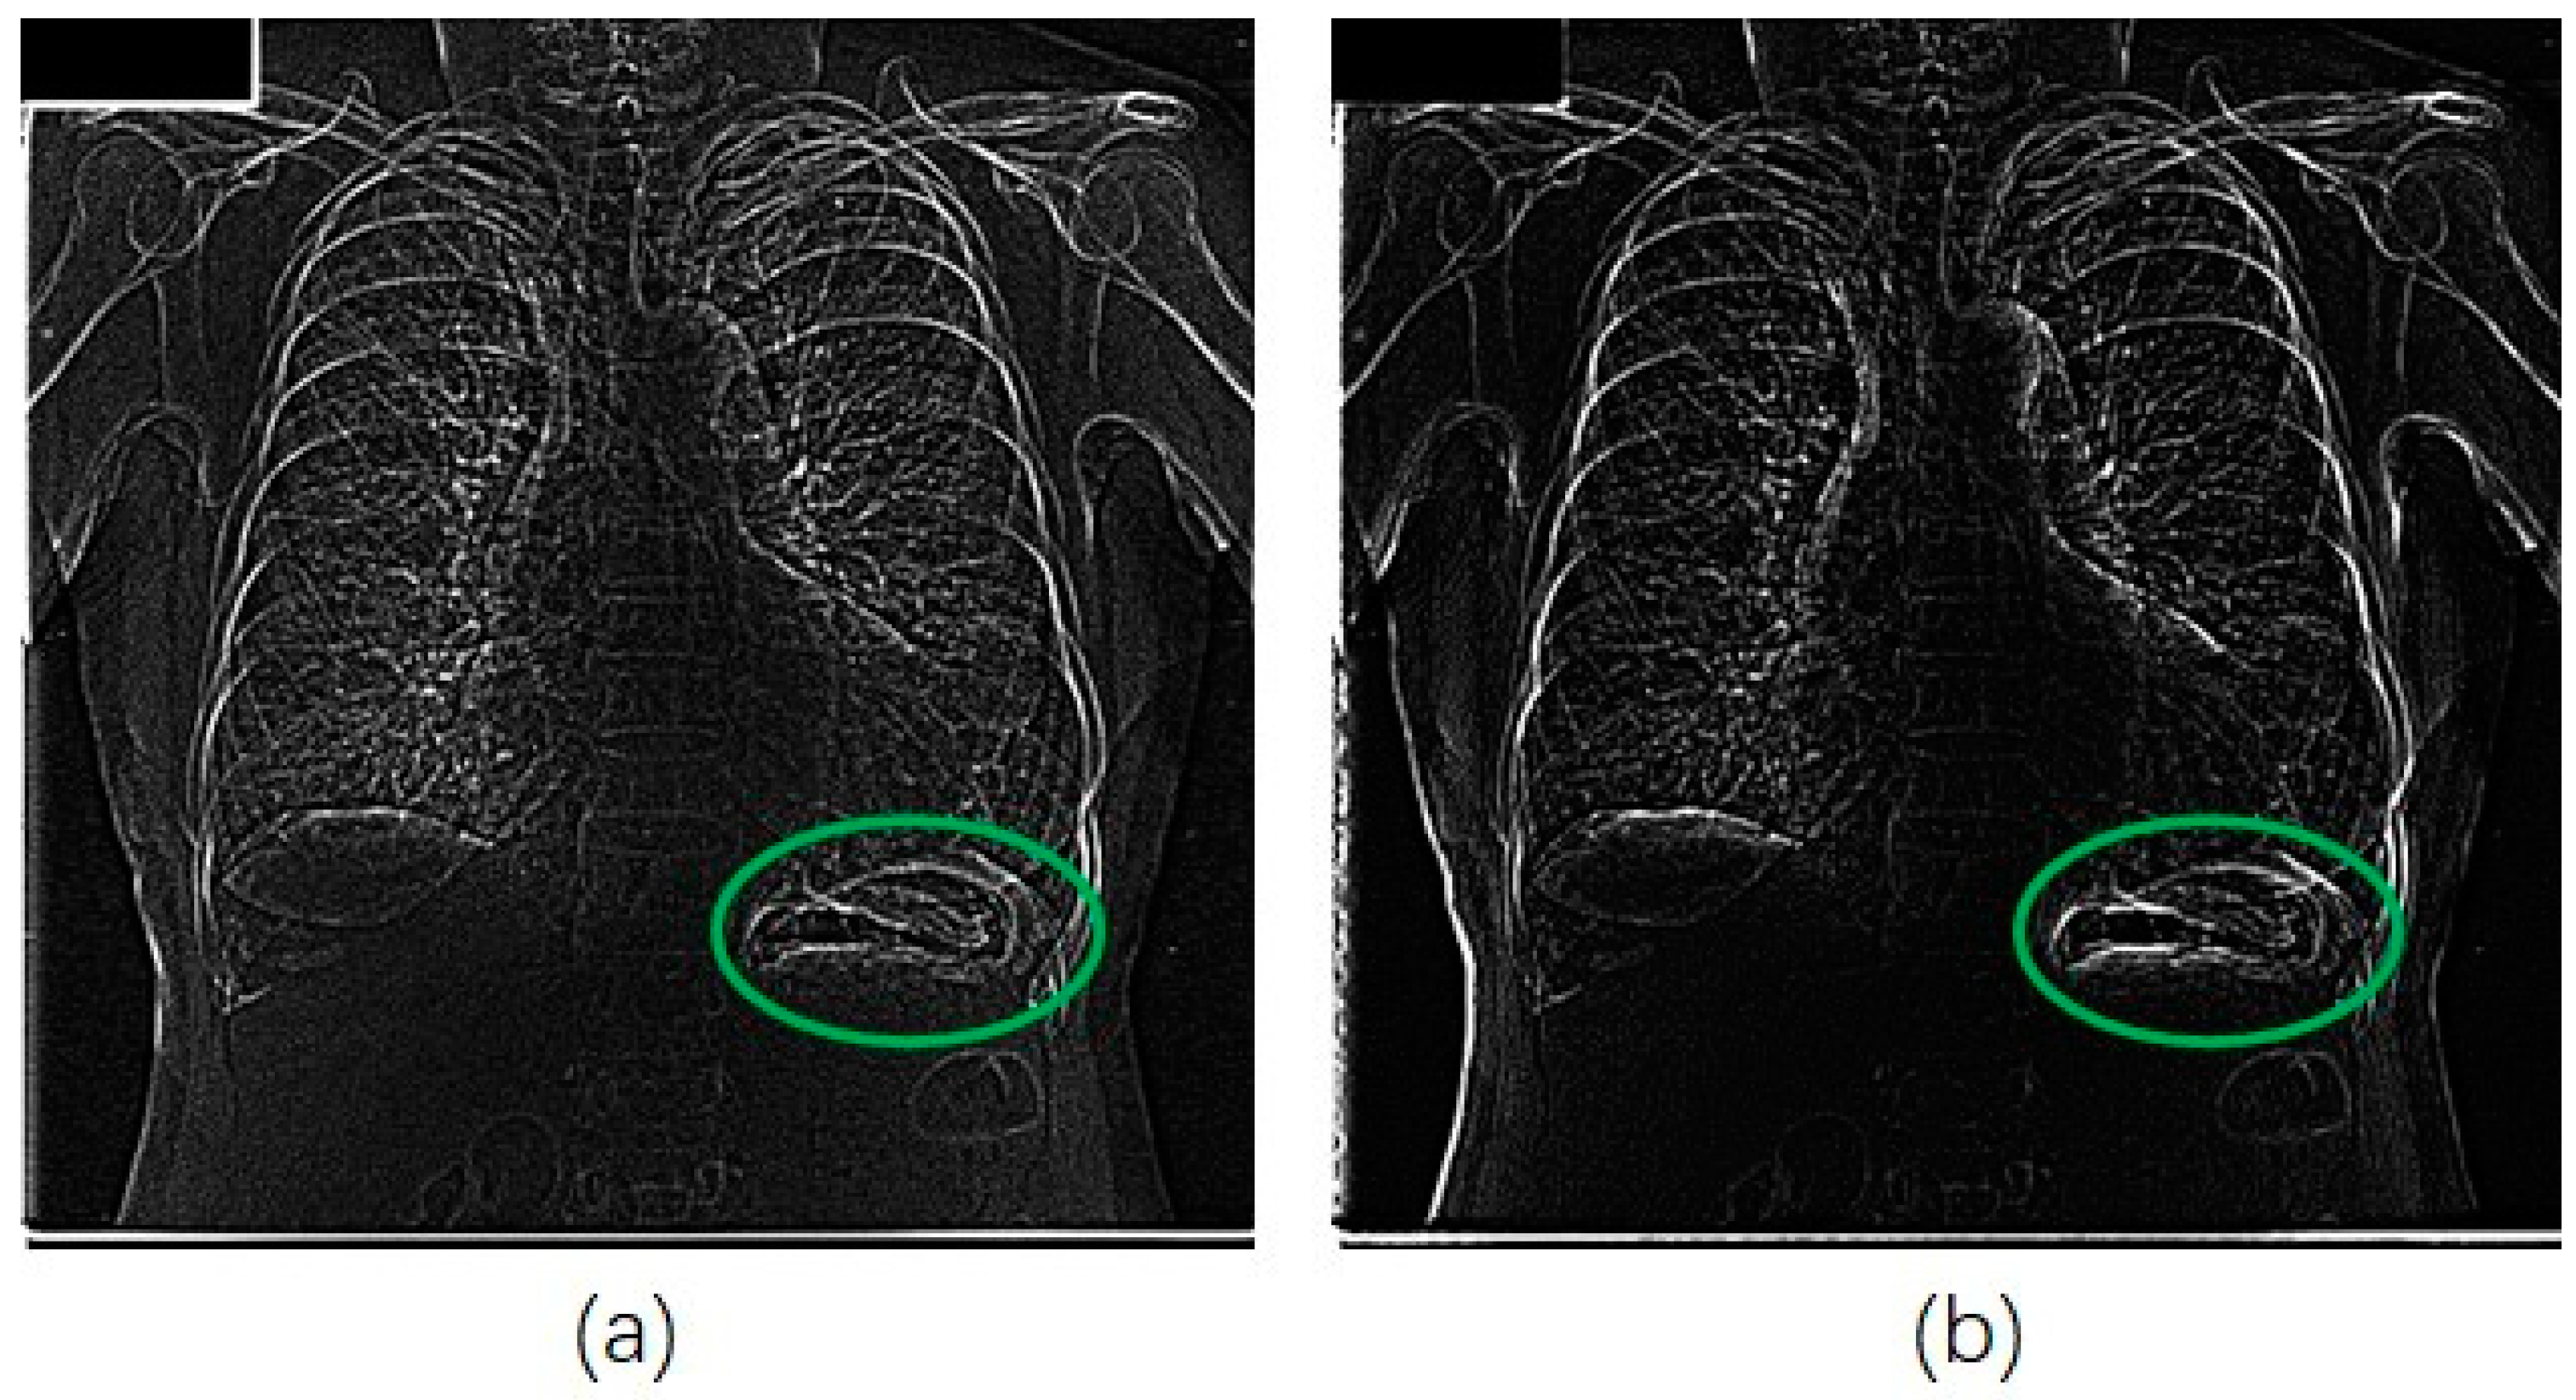

We also applied our method for the JSRT database in a similar manner for that of the portble CXRs database. Figure 7 shows an original image from JSRT database. We can see from Figure 8a that much more noise was created in the unsharp mask by using the Gaussian kernel. The EMEE value for the original CXR was 1.453. Although the EMEE value was improved to 5.643 for the final enhancement image, the noise in Figure 8a was also added in the final enhancement.

Figure 8.

Unsharp masks for image of Figure 7. Green circles are the stomach area, (a) mask from Gaussian difussion; (b) mask from RAD.

When, we applied our RAD-based USM method to this image from the JSRT database, the diffusion parameter α was set to 0.02. Most of the important edge information was reinforced in the unsharp mask with less noise (as shown in Figure 8b).